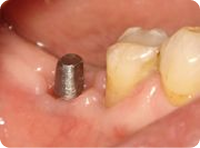

治療中

インプラントの土台を3本植立しました。

手術直後の写真です。